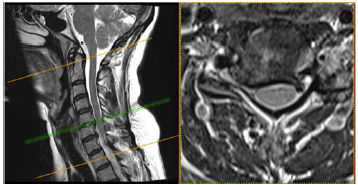

Uma paciente de 47 anos de idade apresenta quadro de cervicobraquialgia direita há cerca de três meses, associada a parestesia no membro superior direito, que se estende até a mão, principalmente nos dedos indicador e polegar. Ao exame físico, nota-se leve redução do reflexo braquioestilorradial. O teste de Spurling foi positivo à direita. Observou-se ausência de paresias.

No citado caso clínico, foi solicitada uma ressonância magnética cervical, conforme representado nas figuras. Esse exame evidencia uma